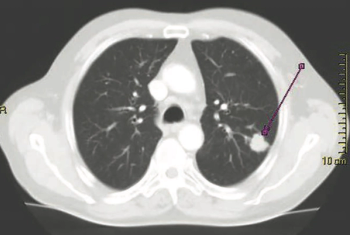

Among participants who were current or former smokers, the NELSON trial found that volume CT screening enabled a significant reduction of harms without jeopardizing favorable outcomes.

The approach was created by the University of Michigan Rogel Cancer Center to limit variability and investigator bias.